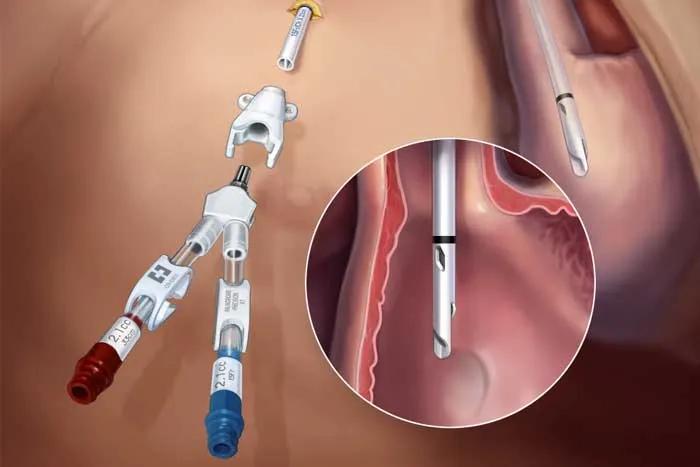

Você sabia que injeções cosméticas podem causar hipercalcemia e insuficiência renal anos após o procedimento? Descubra mais sobre os riscos e tratamentos dessa complicação em nosso novo post no blog!